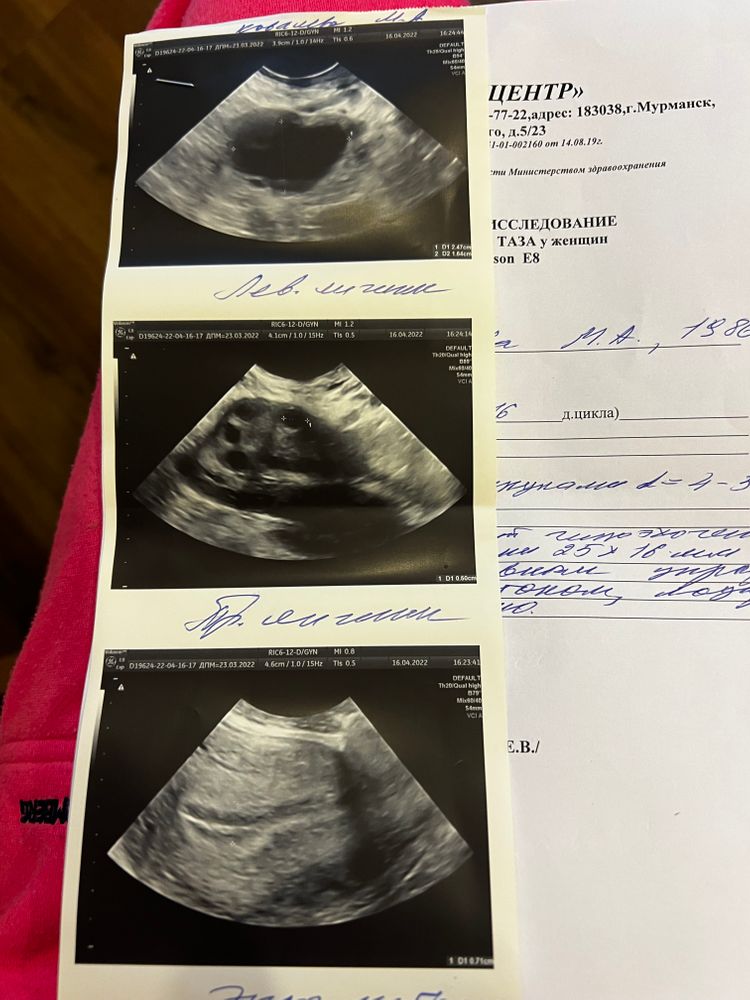

УЗИ 13 ДЦ: Доминирующий фолликул 18*16 мм, эндометрий 8 мм

УЗИ 15 ДЦ: Доминирующий фолликул 21*19 мм, эндометрий 8,9 мм. В этот день 15.04 в 17:30 сделан укол ХГЧ 6000 ед.

УЗИ 16 ДЦ: мой фолликул 25*16 мм, узист сказала, что он как будто сдувшийся, неправильный, и овуляции не будет. Врачу написала, она говорит не факт, больше ничего не сказала. Сказала сходить на узи 18.04, но я не смогу, уехала на три дня в командировку. Перелопатила весь интернет, не понимаю... Это могло быть ведь формирующееся желтое тело?

Первое фото узи на 15 ДЦ, второе на 16 ДЦ